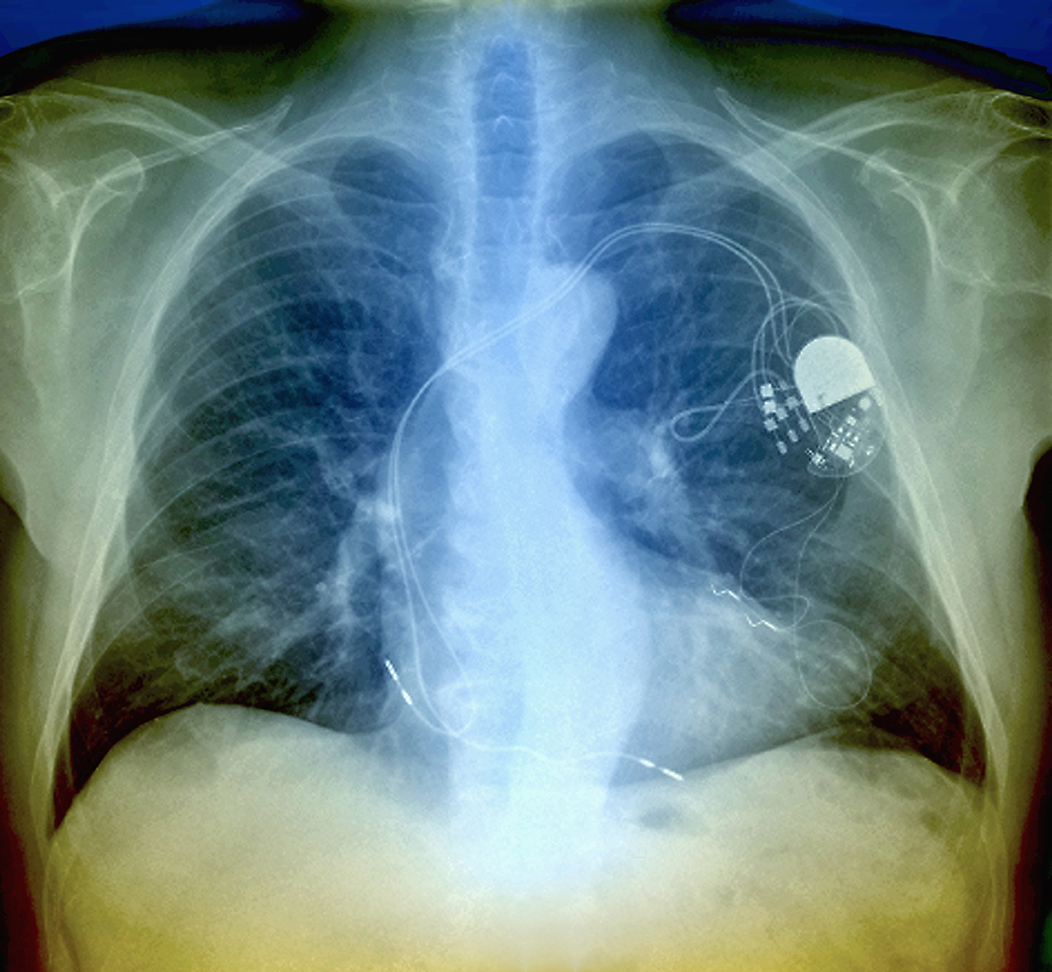

Bayer anunció la adquisición de AT-01 y AT-05, dos agentes de diagnóstico por imágenes desarrollados por la biofarmacéutica estadounidense Attralus, Inc., con el objetivo de fortalecer su cartera de innovación y avanzar en el diagnóstico temprano y preciso de la amiloidosis cardíaca, una enfermedad grave y frecuentemente subdiagnosticada.

Los activos adquiridos incluyen AT-01 (124-yodo-evuzamitida), un trazador PET que se encuentra en fase III de desarrollo clínico, y AT-05, un trazador SPECT en fase I. Ambos están diseñados específicamente para detectar depósitos de amiloide en el corazón y otros órganos, lo que permitiría identificar la enfermedad en etapas más tempranas, cuando las opciones terapéuticas pueden ser más efectivas.

La amiloidosis cardíaca afecta a unas 400.000 personas en todo el mundo y, con los métodos actuales, suele diagnosticarse tarde o pasar desapercibida. En este contexto, AT-01 se destaca por ser el primer agente de imagen pan-amiloide en recibir la designación de terapia innovadora de la FDA en Estados Unidos, además de contar con la designación de medicamento huérfano tanto en EE. UU. como en la Unión Europea.